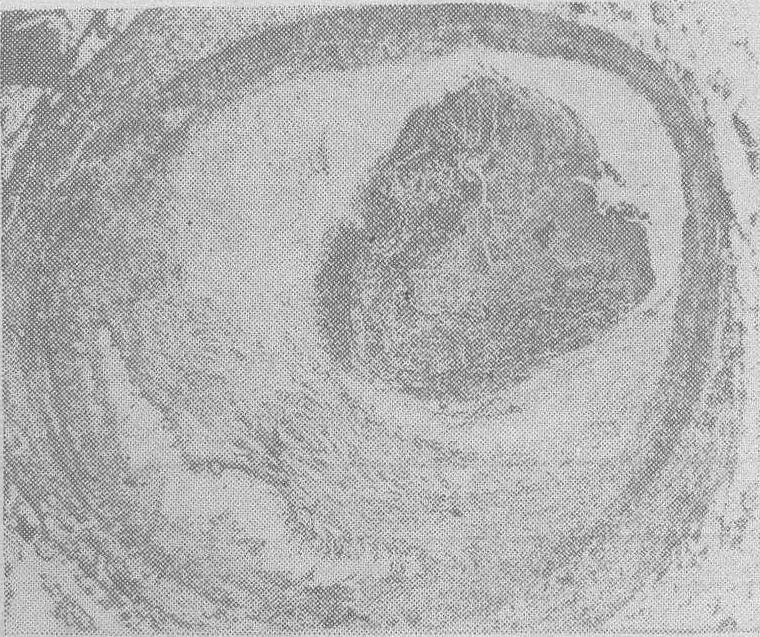

冠心病急死,左前降支3级斑块,并发新近血栓形成

左下斑块底部的针状空隙为胆固醇结晶; 右上斑块表面有新近血栓形成(由血小板及纤维素组成)